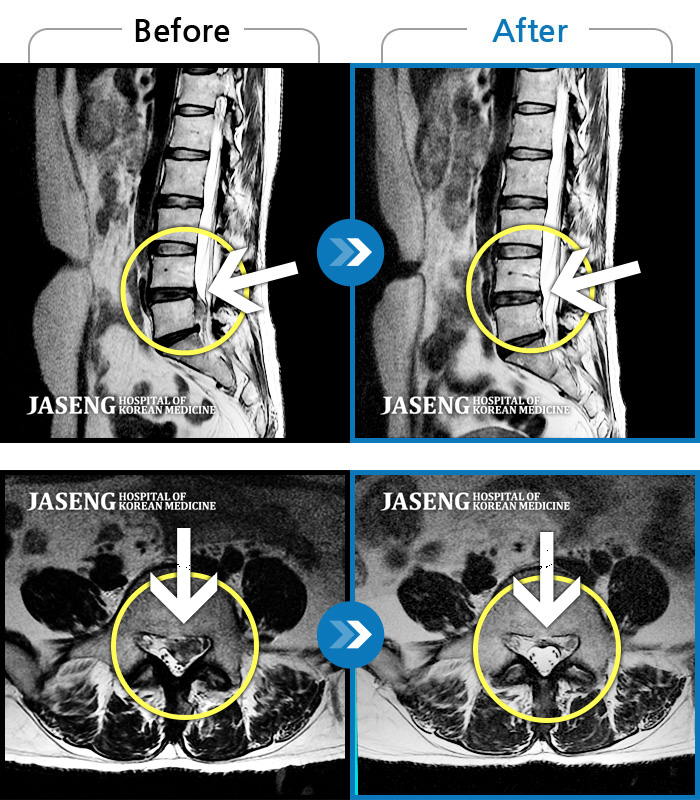

허리디스크

대전 · 김창연 원장

엉덩이의 왼쪽 부위 및 하지방사통이 심각하여 보행이 불가한 상태에서 내원하셨습니다.

촬영시기

2025.01.22 ~ 2025.08.09

2025.08.19

조회수 310